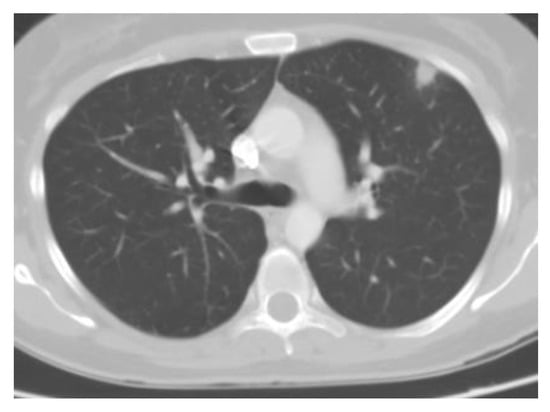

Chest imaging typically reveals diffuse patchy opacities or interstitial infiltrates, which can be associated with hilar and mediastinal adenopathy (Figure 4). Tree-in-bud opacities are less common. Nodules eventually calcify and are the most common finding from prior exposures [52]. Some individuals may develop large nodules, consolidations, acute respiratory distress syndrome, and progressive disseminated histoplasmosis. Of note, patients with disseminated disease often have normal chest imaging [29,53].

Figure 4.

Chest CT of acute pulmonary histoplasmosis showing a large consolidation with air bronchogram.